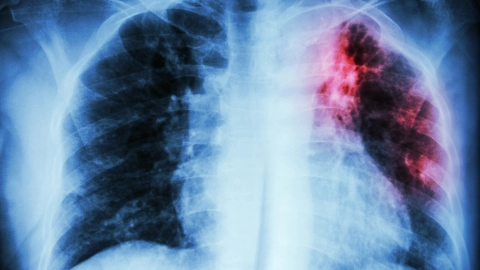

Tuberkulose: Eine Röntgenaufnahme des Brustkorbs. Eine rot-schwarze Verfärbung im linken Lungenflügel weist auf eine Tuberkuloseinfektion hin. Tuberkulose: Eine Röntgenaufnahme des Brustkorbs. Eine rot-schwarze Verfärbung im linken Lungenflügel weist auf eine Tuberkuloseinfektion hin.

Tuberkulose

Tuberkulose ist eine bakterielle Infektionskrankheit, die unter anderem die Lunge befällt. In Deutschland tritt sie relativ selten auf.